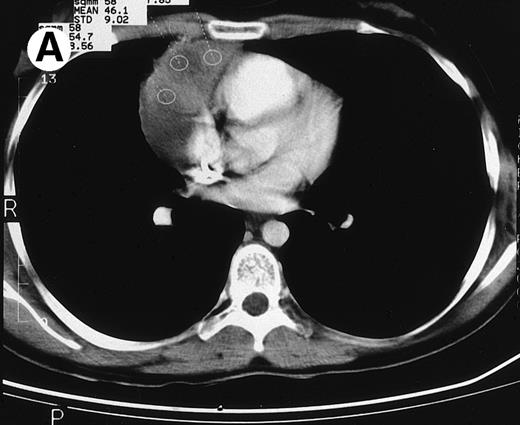

CT and 18F-FDG PET studies at the end of treatment in a case of relapsed HD remaining in clinical CR after a follow-up of 42 months. (A) The CT study at the end of treatment showed a large residual mediastinal mass. (B) The 18F-FDG PET study of this patient was negative.